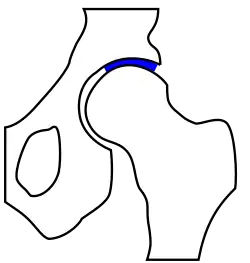

unten: gesundes Hüftgelenk

Das Röntgenbild kann auch Auskunft über präarthrotische Deformitäten, beispielsweise bei einer Hüftdysplasie (vgl. Abb.) als Ursache der Coxarthrose geben.[18] Hier ist der Hüftkopf nicht ausreichend überdacht und steht deswegen dezentriert nach oben / seitlich heraus. Dadurch resultiert eine Verkürzung der Beinlänge. Im Laufe der Zeit kommt es zu einer massiven „Entrundung“ des Hüftkopfes, der Gelenkspalt ist fast ganz aufgehoben, das Hüftgelenk wird steif.